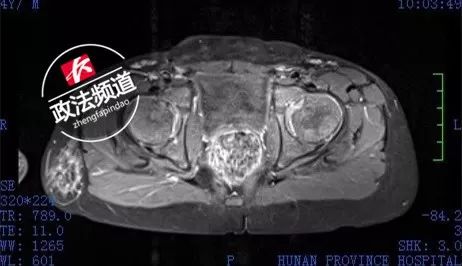

在湖南省人民醫(yī)院兒六科和泌尿三科,徐璇主任和段燚星主任共同分析皓皓的情況,經(jīng)過染色體復(fù)查、基因檢測以及腹部生殖系統(tǒng)增強磁共振檢查、腹腔鏡探查術(shù),專家們發(fā)現(xiàn),皓皓的確只有一套男性的生殖系統(tǒng),沒有子宮,卵巢及卵睪等器官及組織,但男性外生殖器發(fā)育較差,染色體結(jié)果仍然顯示是正常女性的染色體(46XX),基因檢測也顯示他的SRY基因(又叫男性性別決定基因)為陰性,其他基因檢測也與正常女性并無差異。